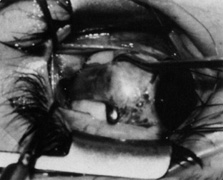

Step 3. Two double-armed 6-0 Vicryl sutures are used to secure each half of the muscle separately (Fig. 4). Both halves of the muscle are disinserted from the sclera (Fig. 5).

Fig. 4. Two double-armed 6-0 Vicryl sutures are used to secure each half of the muscle separately.

Fig. 5. Both halves of the muscle are disinserted from the sclera.